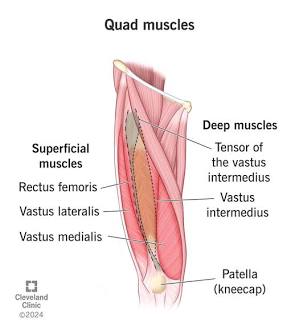

Quadriceps

Four origins.

Vastus

Great.